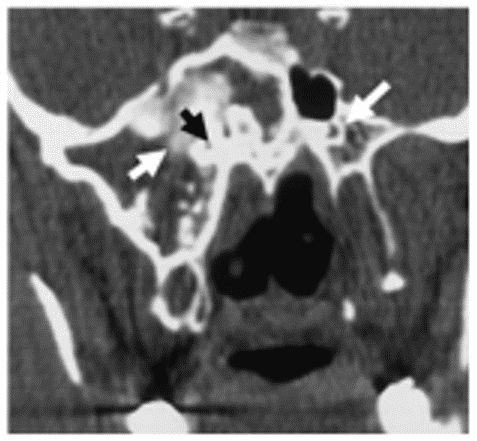

При фиброзной дисплазии тела клиновидной кости в первую очередь поражается сфеноидальный синус, далее процесс обычно распространяется на большое крыло клиновидной кости, крыловидный отросток, малое крыло, площадку клиновидной кости и другие анатомические структуры. Возникающие при этом деформация и сужение овального и круглого отверстий, нижней глазничной щели, зрительного и видиева каналов (рисунок 7), компрессия расположенных в непосредственной близости черепных нервов и крупных сосудов сопровождаются соответствующей клинической симптоматикой, что является непосредственной причиной визита такого пациента к врачу.

Рис. 7. КТ околоносовых пазух, аксиальная (А) и коронарная (Б) проекции. Фиброзная дисплазия клиновидной кости. Б-патологический процесс распространяется на большое крыло клиновидной кости (стрелка) и крыловидный отросток; асимметрия видиевых каналов - на стороне поражения он резко сужен (стрелки)